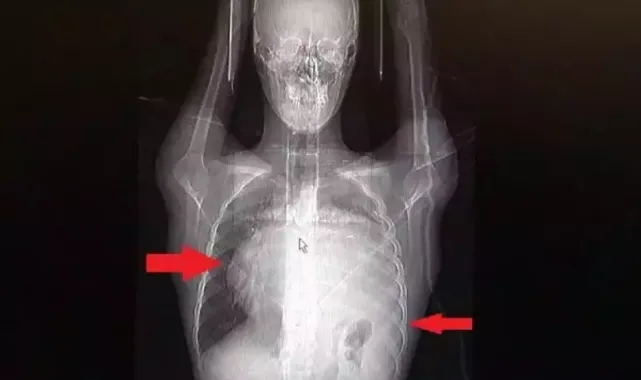

Kalbini göğüs boşluğunda 12 santimetre sağa iten, sol akciğerini neredeyse tamamen ezen dev tümör, Koşuyolu Yüksek İhtisas Eğitim ve Araştırma Hastanesi Göğüs Cerrahisi ve Kalp Damar Cerrahisi ekiplerinin beraber katıldığı büyük bir operasyonla başarıyla çıkarıldı. Bu kadar hızlı büyüyen kitle karşısında doktorları da şaşırdı.İstanbul’da yaşayan 21 yaşındaki Burak Aktaş, Temmuz ayında işe girmek üzere sağlık raporu almak için hastaneye gitti. Herşey yolundaydı ve raporunu alarak iş başı yaptı. Bir ay geçmeden nefes darlığı, halsizlik, öksürük gibi şikayetlerle başka bir hastaneye gittiğinde ise ilk şoku yaşadı. Sol göğüs boşluğunda portakal büyüklüğünde bir kitle tespit edilmişti. Yapılan biyopside tümörün akciğer kaynaklı olmadığı, henüz cenin aşamasında eşey hücrelerinin farklılaşmasıyla gelişen “immatür teratom" teşhisi kondu. Kitleyi küçültmek için kemoterapi uygulansa da tam tersine tümör 2 ay içinde neredeyse 10 katına çıktı ve büyük bir karpuz boyutuna ulaştı. Sol akciğerinin yüzde seksenini kağıt gibi ezen, kalbini göğüs duvarında 12 santim sağa kaydıran ve hem kalbe hem beyne giden ana damarlara baskı yapan 6.5 kilo ağırlığındaki dev tümör, Koşuyolu Yüksek İhtisas Eğitim ve Araştırma Hastanesi Göğüs ve Kalp Damar Cerrahisi ekiplerinin birlikte girdiği operasyonla başarılı şekilde çıkarıldı. Operasyon sırasında Aktaş’ın kalbi normal yerine çekildi, sol akciğerin üst lobu alındı, ezilen alt lobu ise anestezi ekipleri tarafından pozitif basınçla yeniden şişirildi. Ameliyatı gerçekleştiren ekipten Prof. Dr. Erdal Taşçı, Aktaş’ın göğüs boşluğunun neredeyse tamamını kaplayan 6,5 kiloluk tümörün teratom (eski Yunancada ‘canavar tümör’) türlerinden biri olduğunu ve embriyonik hücrelerden kaynaklandığını kaydetti.

Prof. Dr. Erdal Taşçı, "Bundan 2,5-3 ay öncesine kadar hiçbir problemi olmayan, hayatını normal devam ettiren bir delikanlı Burak. Göğüs ağrısı öksürük ve nefes darlığı şikayetiyle sağlık kuruluşuna başvuruyor. Orada yapılan tetkiklerinde sol göğüs boşluğunda akciğerinden kaynaklanmayan portakal büyüklüğünde bir kitle tespit ediliyor ve immatür teratom tanısı konuyor. 2 ay arayla yapılan tetkiklerinde ve arada cerrahi öncesi küçültme amaçlı kemoterapi almasına rağmen, portakal büyüklüğündeki tümör, irice bir karpuz büyüklüğüne, yaklaşık 6 kilo 300 grama kadar ulaşıyor. Göğüs boşluğunda kemik kafesi içinde olduğu için, itebileceği iki organ var; biri kalp, diğeri de akciğerler. Soldan sağa doğru büyüdüğü için kalbi tamamen göğüs boşluğunun sağ tarafına itmiş ve kalbe giren ve kalpten çıkan bütün büyük damarları da yer değiştirmenin etkisiyle bükülmüş durumdaydı. Bu nedenle vücuduna yeterince kan gitmiyordu. Ağustos ayının başında portakal büyüklüğündeyken kitle Eylül sonuna irice bir kavun, Ekim ayına geldiğimizde ise bir karpuz büyüklüğüne ulaştığı için, kitlenin büyüme hızı bizi acilen ameliyat yapmaya yöneltti. Yaklaşık 8-10 kat hacimsel olarak artmıştı. Sol akciğer tamamen ezilmiş ve kağıt haldeydi, alt lobu anestezi ekibimiz yüksek basınç uygulayarak tekrar şişirdi. Çok fazla vaktimiz yoktu, kitle basısından dolayı yaşamla bağdaşmayacağından dolayı hızlı hareket etmek zorundaydık. Bize geldikten üç gün sonra hemen ameliyata aldık çünkü tümörden ziyade onun yaptığı baskıdan kaynaklı hayati riski vardı" dedi.

Normalde kalbin özellikle alt ucunun göğüs boşluğunda, iman tahtası orta çizgi kabul edilirse, sola bakar şekilde durduğuna dikkat çeken Prof. Dr. Taşçı, sözlerini şöyle sürdürdü: "Ama bu hastada yaklaşık 12-13 s santimlik kalbin alt ucununu yer değiştirmesi ve kalbe giren çıkan bütün damarlar bükülüp kan akımı bozulmuştu. kalp Damar Cerrahisi ekibi de bizimle beraber ameliyata girdi. Sol akciğerin üst lobu artık geri dönüşümsüz olarak ezildiği için çıkarmak zorunda kaldık. Kalbi tekrar eski pozisyonuna getirdik. Ameliyat sonrası çok çabuk toparladı. Koşuyolu ailesi olarak böyle büyük bir vakanın altından başarıyla çıktığımız için de ayrıca çok gururluyuz. Bundan sonra onkolog arkadaşlarımız hastamızın yaşamına çok olumlu dokunuşlar yapacak. İmmatür teratom genelde embriyojenik çağda gelişim gösteren germ hücrelerinin farklılaşmasıyla büyür. Vücudun herhangi bir yerinde gelişebilir ve içinde saç, diş, kemik artıkları, jölemsi kıvamda maddeler bulundurabilen bir tümör çeşididir. Kombine tedavilerde çok iyi sonuçlar alınıyor. Bu çocuğumuzu ileride güzel bir hayat bekliyor."